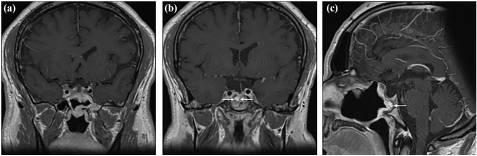

术后患者出现短暂的中枢性肾上腺功能不全和中枢性尿崩症,需要使用氢化可的松和去氨加压素进行临时治疗,并在接下来的八个月内成功地逐渐减量。术后三个月的促肾上腺皮质激素刺激试验显示,皮质醇峰值在60分钟时为701 nmol/L,排除了中央肾上腺功能不全,支持氢化可的松减量。术后7个月的夜间禁水试验显示,血清钠为141 mmol/L,血清渗透压为289 mOsm/kg,尿液渗透压为665 mOsm/kg,因此排除中枢性尿崩症,允许停用去氨加压素。术后18个月,患者垂体前叶和垂体后叶功能正常,垂体激素水平正常。随访MRI显示,颈内动脉周围的右侧海绵窦中只有一个小的残留肿瘤信号,尺寸为4×15 mm(图3)。患者报告术后头痛部分缓解。

图3 术后MRI。冠状(a,b)T1钆后MRI显示肿瘤切除,包括延伸到海绵窦的部分。矢状重建(c)显示蝶鞍鼻中隔皮瓣的重建